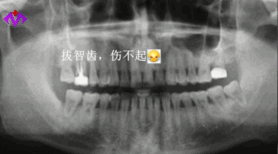

如果你是拔智齿或者是早期因为蛀牙需要治疗的补牙、牙周炎、牙龈炎等,医保是可以报销一部分费用的。不过牙科医保报销的自费比例也比较高,像慢性牙髓炎、慢性根尖炎、慢性牙周炎,自费比例在55%左右。